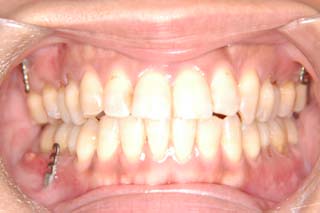

(開咬/叢生/非抜歯/リンガルブラケット矯正装置)

装置撤去です。動的処置は2年弱でした。十分とは言えない点もありますが、患者希望による非抜歯配列でしたので、概ね良好と言える結果が得られたと思います。まだ、オーソアンカー SMAPがそのまま残っているのが見えますが、もう必要ないので撤去して貰う予定です。今後は保定治療に移行し、咬合の安定状態を管理していきます。